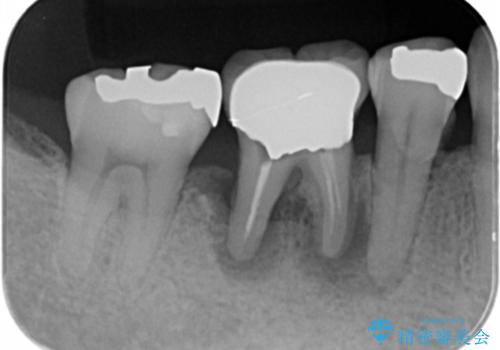

- 歯茎が腫れて痛いとの事で来院。

保存できない状態でしたので抜歯をして歯槽堤保存術を行いました。その後大臼歯部にインプラント治療を行いました。

欠損部に1本だけインプラントを埋入しても大きな被せ物になってしまい清掃性が悪くなるので清掃性が良くなるように2本小臼歯用のインプラントを埋入しました。